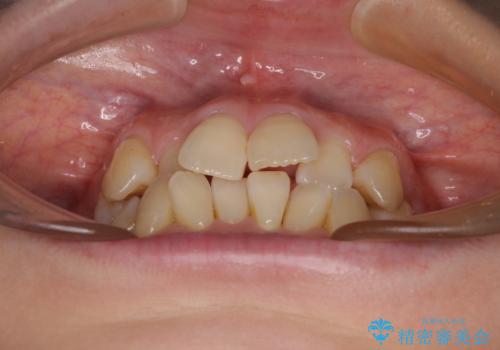

前歯のデコボコをインビザラインで目立たずに改善

- 上下前歯のデコボコを気にして来院された患者様です。

デコボコは顕著であるものの、口元の突出感は強くないため、非抜歯にて矯正治療を行うこととしました。

装置はワイヤー装置でもマウスピースでも対応可能でしたが、より目立たない装置をご希望とのことで、インビザラインにて矯正治療を行うこととしました。

元々の叢生と歯肉退縮傾向になる歯肉であったため、ブラックトライアングルが目立つことが想定されました。

治療過程でブラックトライアングル改善のため、IPR(歯と歯の間を削る)を活用しました。